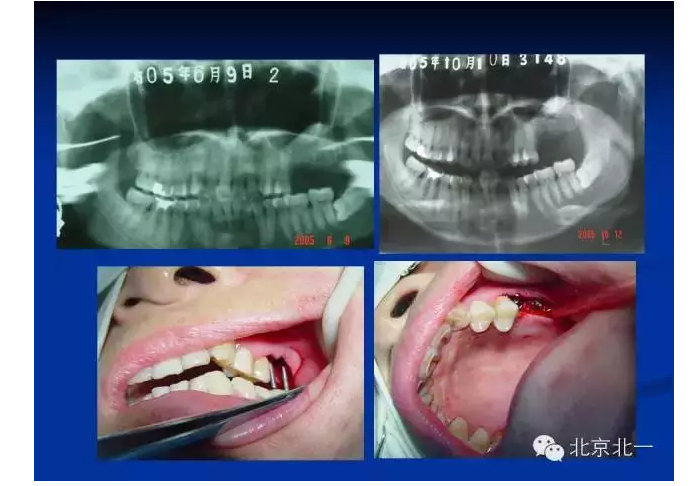

擅長:種植外科,尤其專長復(fù)雜牙種植,自體骨移植同期種植,上頜竇底內(nèi)外提升同期種植技術(shù),美學(xué)區(qū)種植技術(shù),即刻種植外科與即刻負(fù)重技術(shù),軟組織成形外科種植技術(shù)及全口無牙頜ALL-ON-FOUR技術(shù),種植并發(fā)癥和種植急癥處置等手術(shù)治療,從事口腔頜面外科,正頜外科、頜面部整形、微創(chuàng)拔牙,笑氣無痛舒適種植十余年。